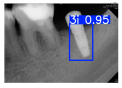

| Image Resolution = 825 × 1200 | ||||

|---|---|---|---|---|

| Test Image 1–4 | ![]() | ![]() | ![]() | ![]() |

| Accuracy | 94.13% | 95.29% | 92.88% | 91.80% |

| Recall | 96.71% | 94.03% | 93.88% | 92.15% |

| Model reference time | 6.57 ms | 7.08 ms | 7.12 ms | 6.43 ms |

| Dentists’ average diagnostic time | 2.78 s | 4.55 s | 7.78 s | 7.23 s |